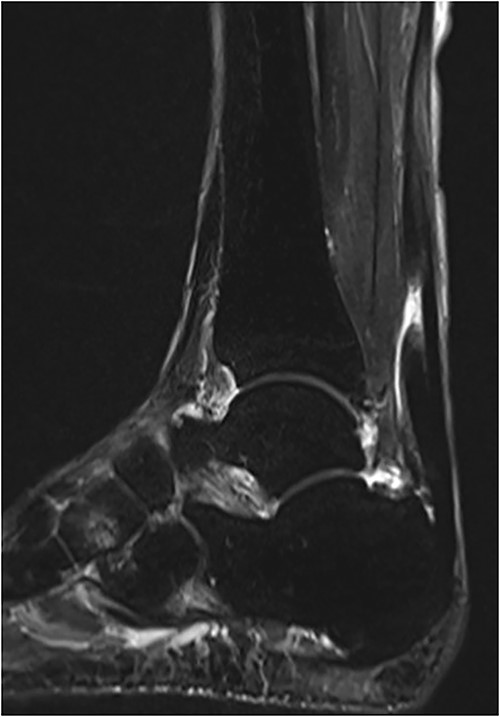

A 75-year-old male presented to a local clinic complaining of right heel pain after spraining his right ankle. He was diagnosed with an ankle sprain and treated conservatively for 2 months. However, the heel pain did not improve and so he visited our hospital. Physical examination revealed a palpable gap along the course of the Achilles tendon and a positive Thompson test. Plain radiographs showed no abnormalities, but MRI revealed a rupture of the Achilles tendon with a gap between the tendon ends (Fig. 3). Based on physical examination and imaging findings, we diagnosed the patient with chronic ATR and administered surgical treatment.